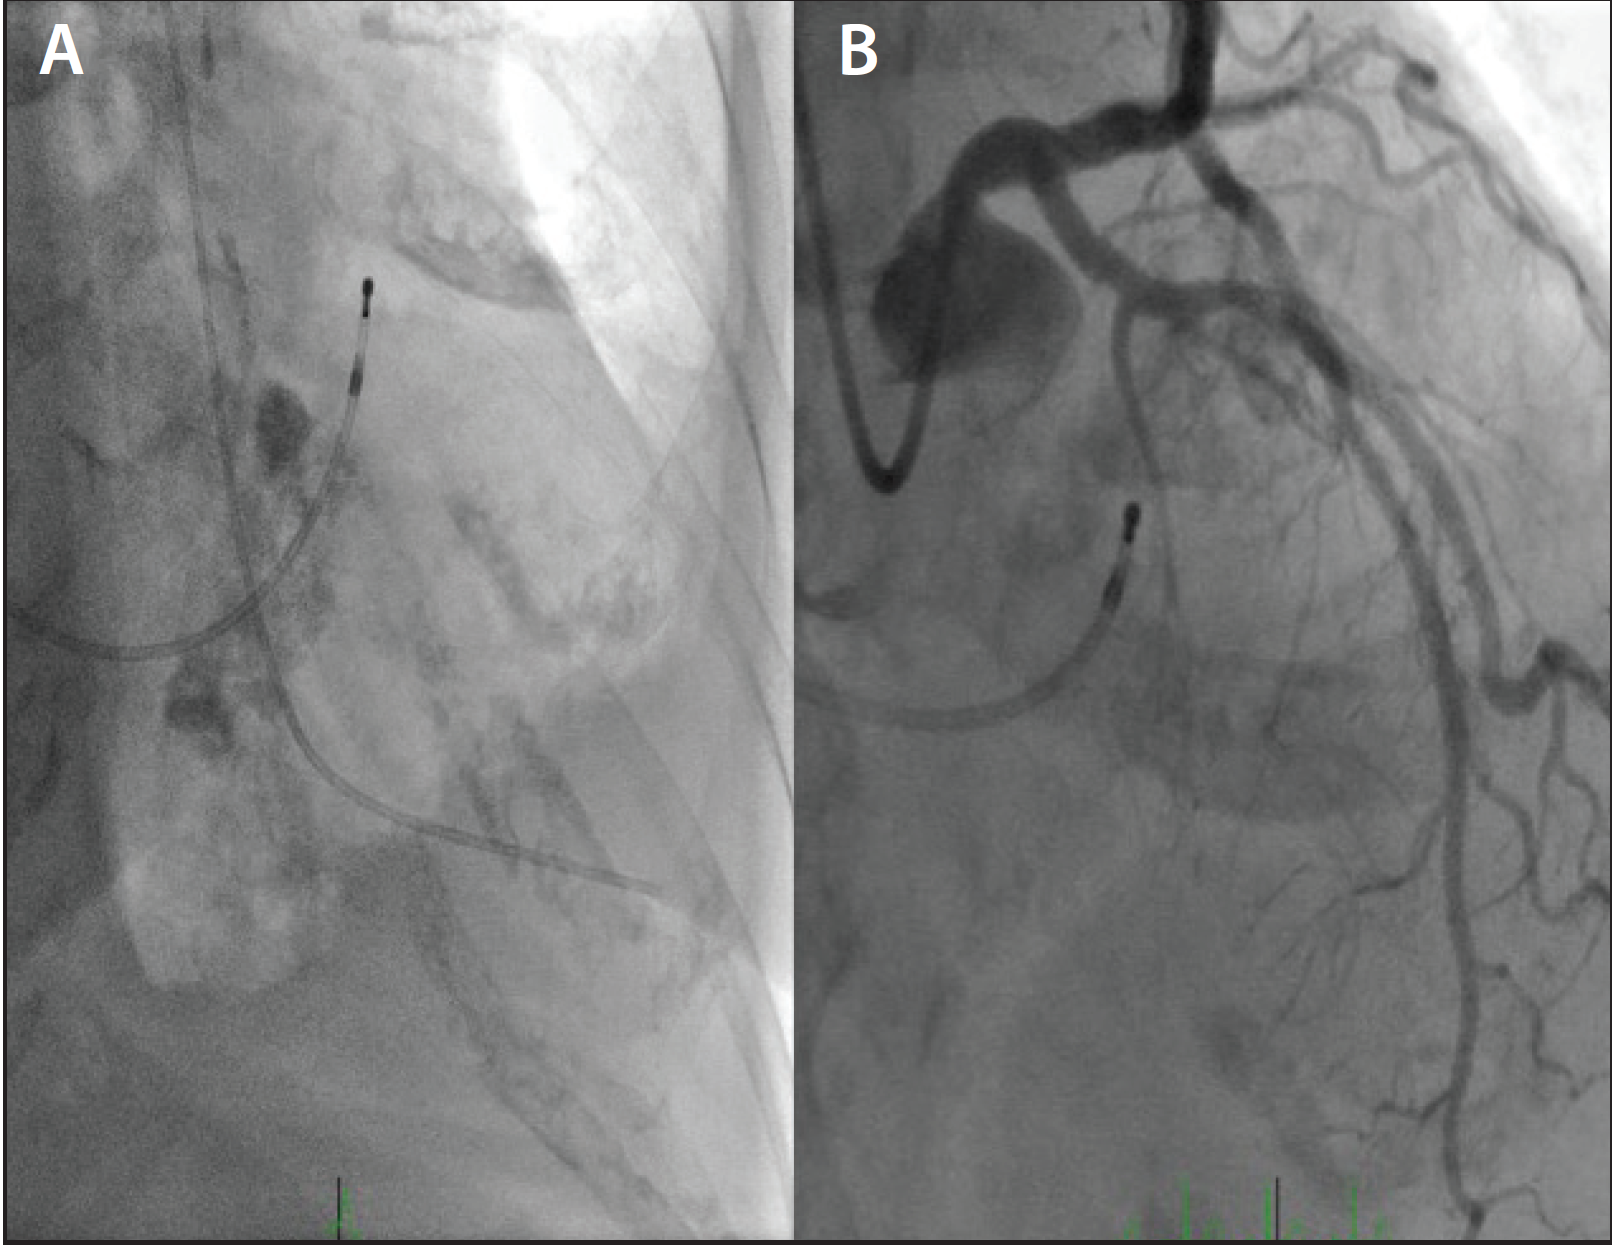

Figure 1. A transvenous pacer was inserted from the basilic vein access, and a dual-lumen multipurpose catheter was inserted via the right RA (A). Extra backup guide from the right radial was used to perform septal ablation, and the first septal artery was obliterated with an alcohol injection (B).

A recent publication from a single-center retrospective review concluded that ASA from the radial approach could be performed with similar acute and long-term success, but with lower vascular complications compared to the femoral approach.5 This procedure is in very close simulation to transradial (TR) coronary intervention. The transvenous pacer can be used either from the AVA or neck vein (jugular/subclavian) approach. In an example shown in Figure 1, a 63-year-old man was treated for symptomatic, hypertrophic, obstructive cardiomyopathy. Right basilic vein access was used to place a transvenous balloon tip pacing catheter. Right RA and a dual-lumen, multipurpose shape Langston catheter (Vascular Solutions, Inc.) was used to measure the gradient across the left ventricular (LV) outflow track before and after septal ablation. The first septal artery ablation was performed using an extra backup 3.5-F guide catheter and injecting 2 mL of alcohol.